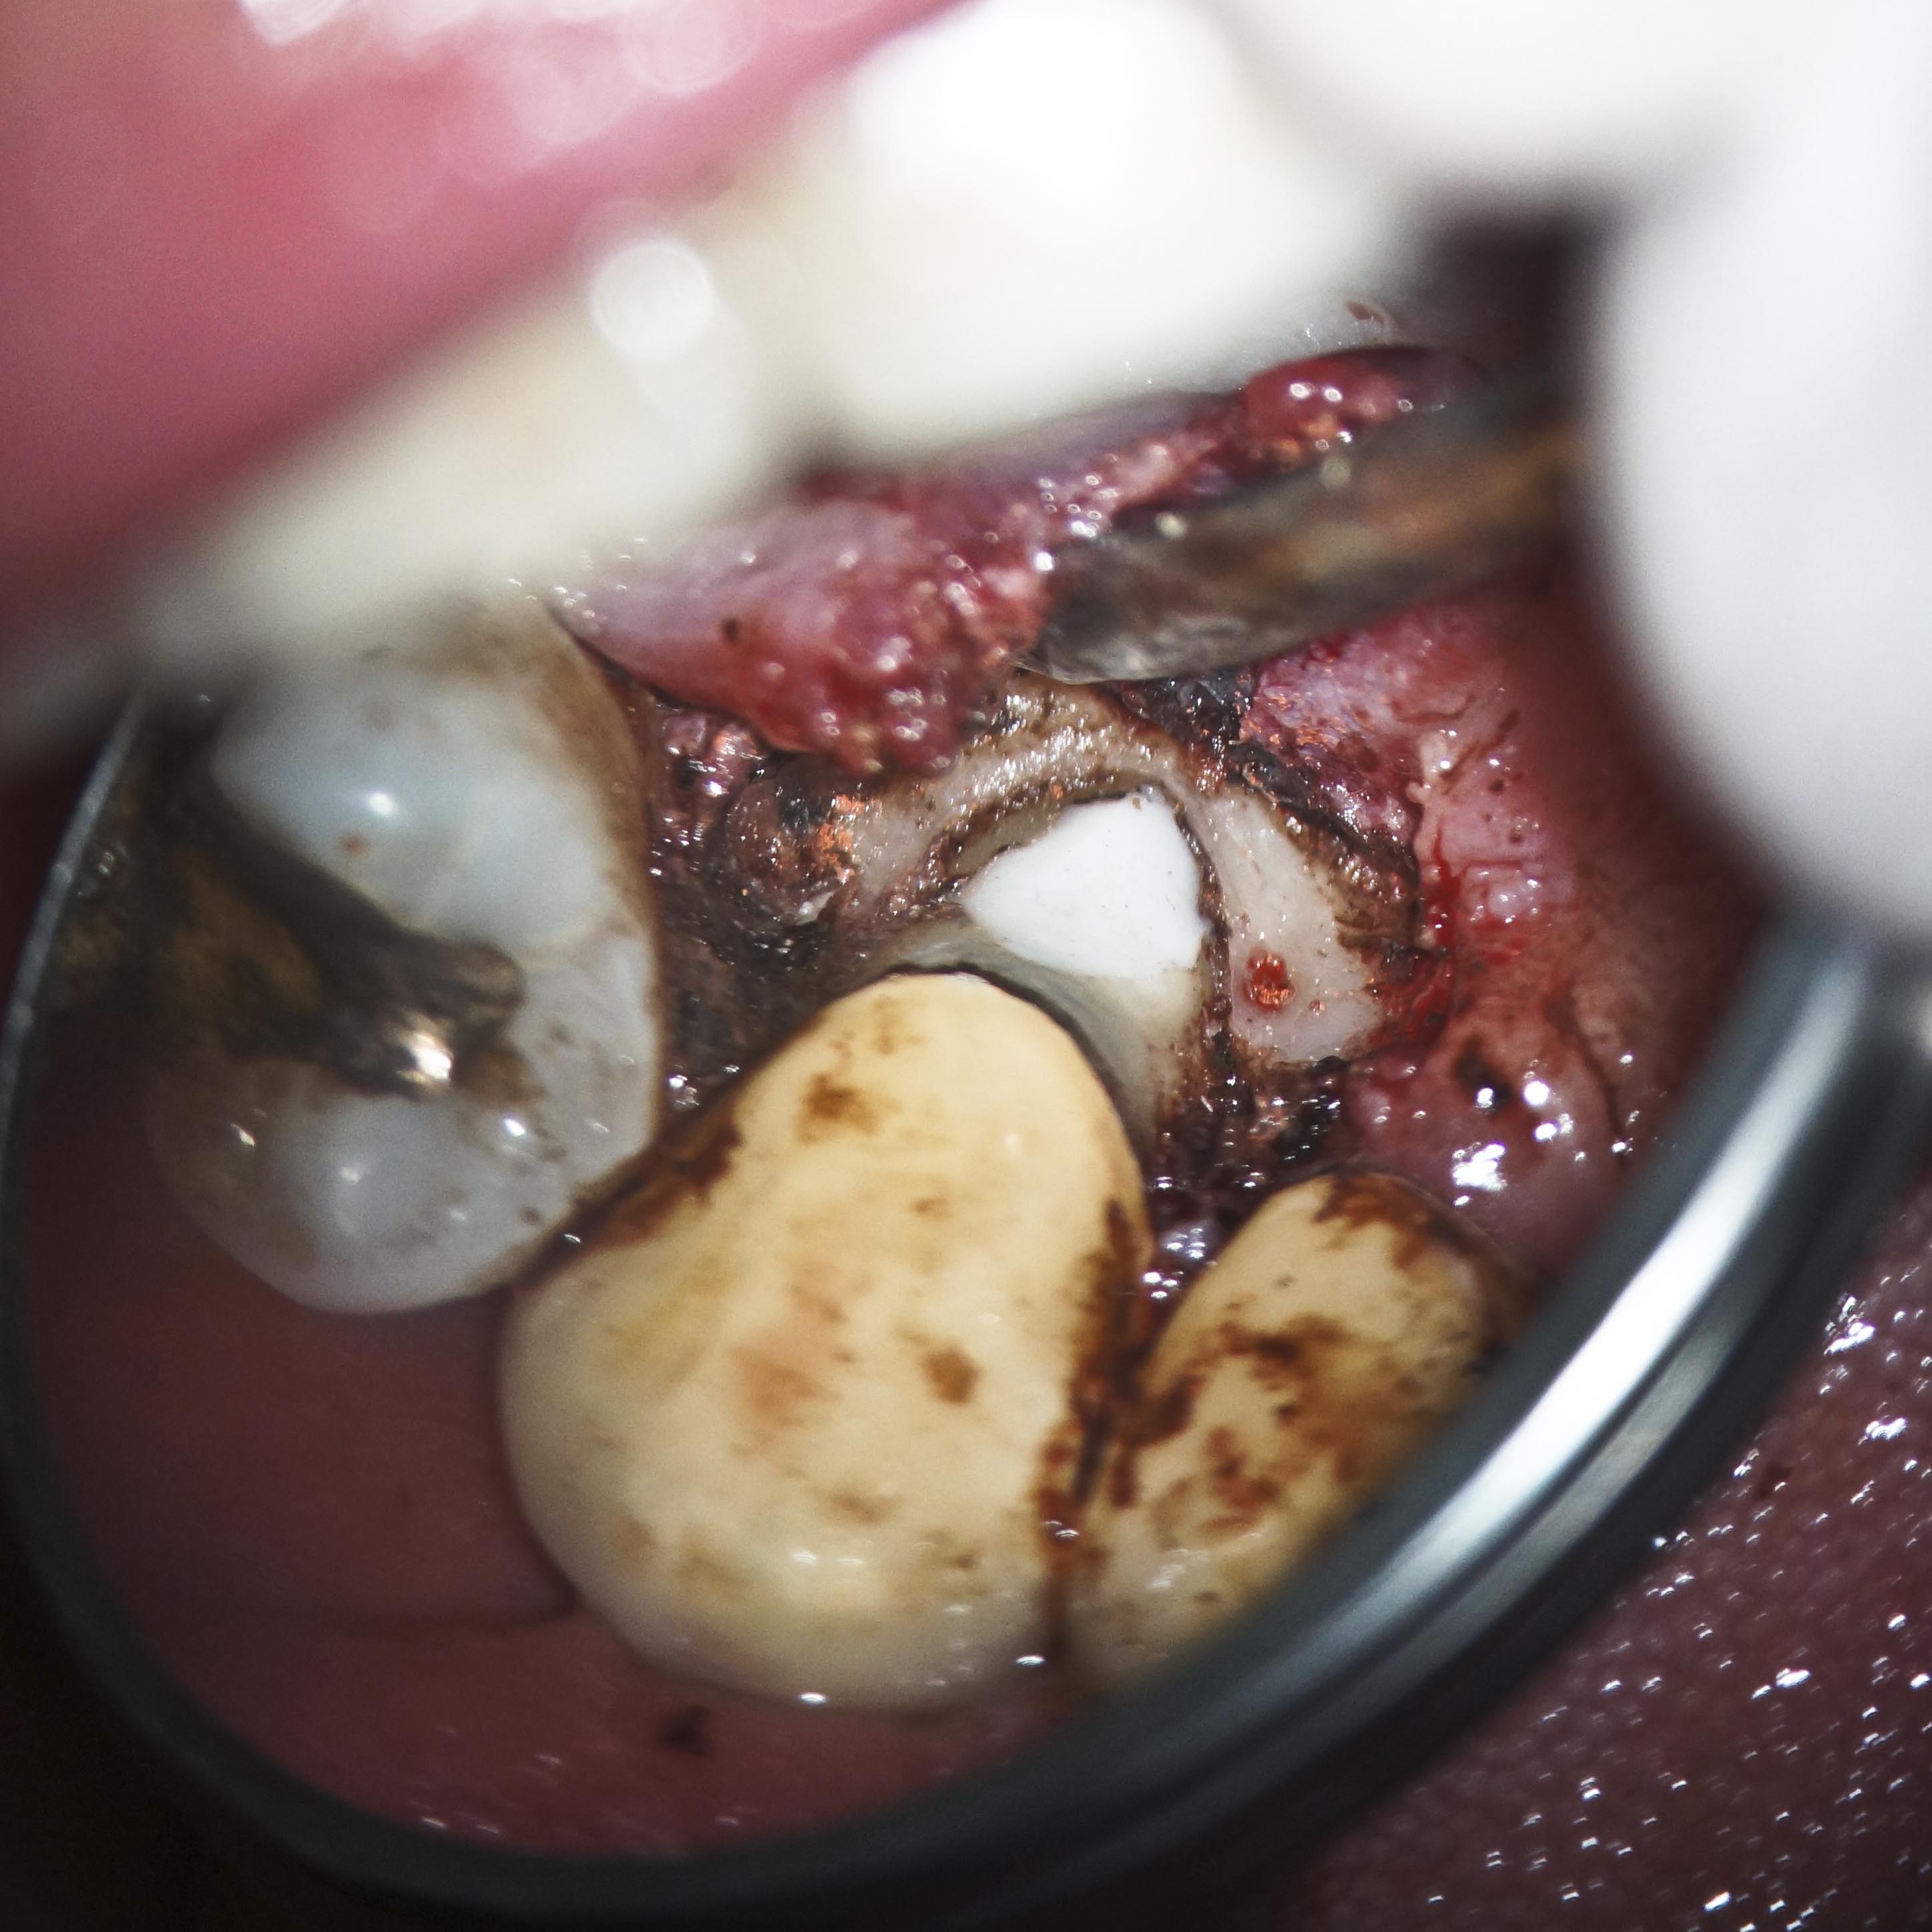

ER-5 Veröffentlicht 17. Juni 2013 am 2894 × 2894 in Was zeigt das DVT (4) – Resorptionen – Die Antworten – Fall 1